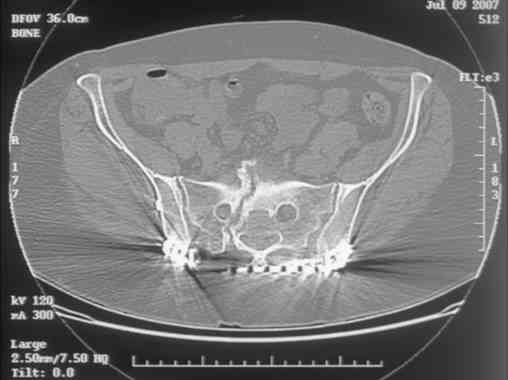

Re: Sacral Non-Union

Here is a magnified view. Sorry about the quality but the CT was scanned into our system.

dave